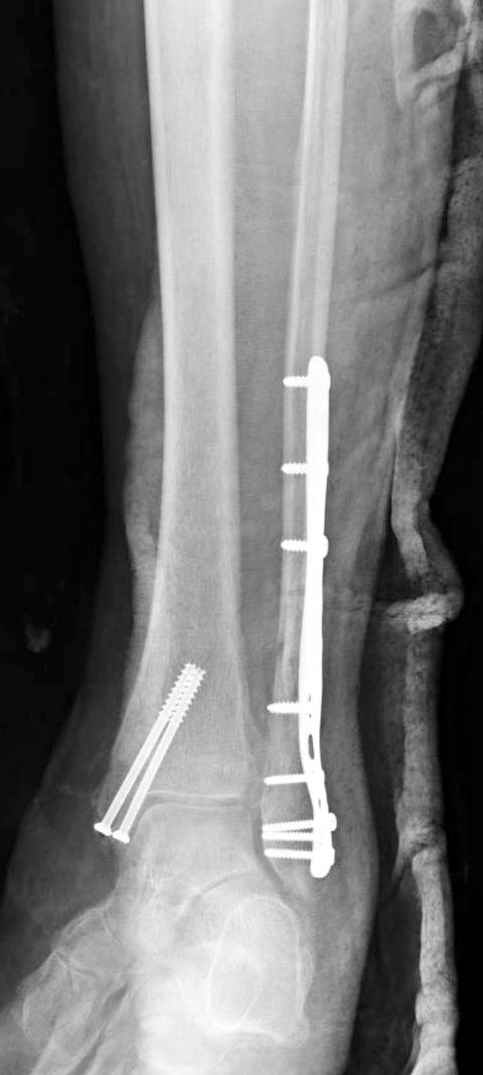

На 4-й неделе убрал спицы, с 7-й недели начал ЛФК, дозированную нагрузку, физиопроцедуры, массаж. Назначил хондропротекторы. Получилось вот что.

Rg-05.JPG

Удалены спицы, а гипса не было? 3-х лодыжечный перелом фиксировать 4 недели недостаточно. Что и подтверждается на последнем снимке - есть тенденция к подвывиху кнаружи, кзади... Что будет дальше, когда пациент начнет давать полную нагрузку?

Малоберцовая выглядит коротковатой. Профиль как-то мутный. Вообще, неплохо было бы сделать снимки в сравнении со здоровой.

Конечно, малоберцовая укорочена, надо сделать косой - мортиз снимок, тогда будеть понятно, на сколько.

Здесь финальный снимок 73 летней с

сопутствующей шизофренией, латерально бридж

пластину (соединили дистальный конец с диафизом не трогая место перелома) и медиально перкутанно

двумя шурупами. В этам случае без гипса не

обойтись.

Получился ожидаемый результат. Недостаточная длительность иммобилизации - подвывих, а жаль, первичная репозиция была замечательная, целесообразность назначения хондропротекторов, физиопроцедур вызывает сомнения.